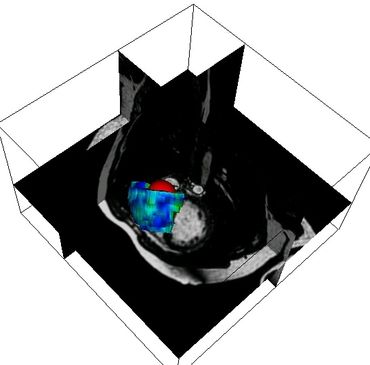

Procesamiento de Imágenes Vectoriales y 4D MRI - Medical Image Analysis (MIA99) (pdf)

DescargarEcocardiografía 3D+T- Transactions on Medical Imaging (TMI02) (pdf)

DescargarIntervención: Electro-Fisio XMR Ablación (FMIH05) (pdf)

TODOS LOS CÁLCULOS, IMÁGENES Y ANIMACIONES en esta página y artículos, fueron producidos con PROGRAMAS ESCRITOS POR MI en C / C++ y VTK/TCL/TK